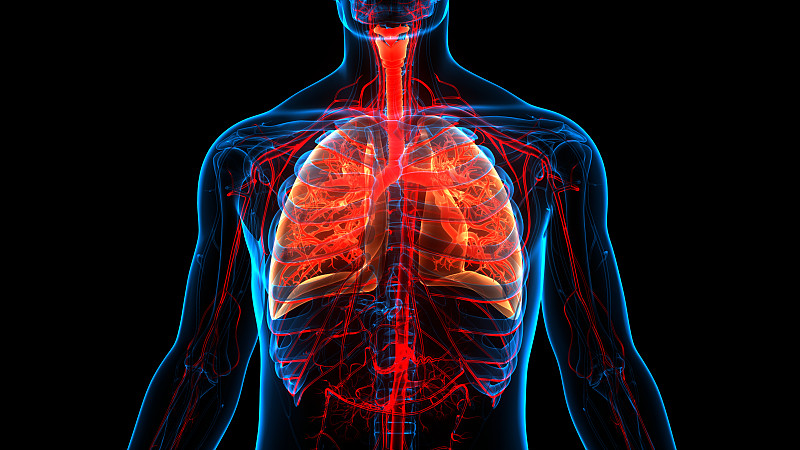

人体呼吸系统肺解剖学详情

JPG